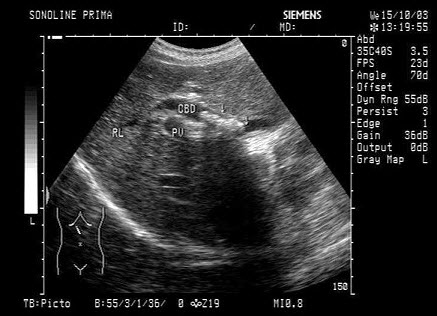

10、单项选择题

某患者右下腹痛,血尿,根据超声声像图,最可能的诊断为()

A.右肾结石

B.右输尿管下段结石

C.阑尾炎

D.膀胱结石

E.输尿管肿瘤